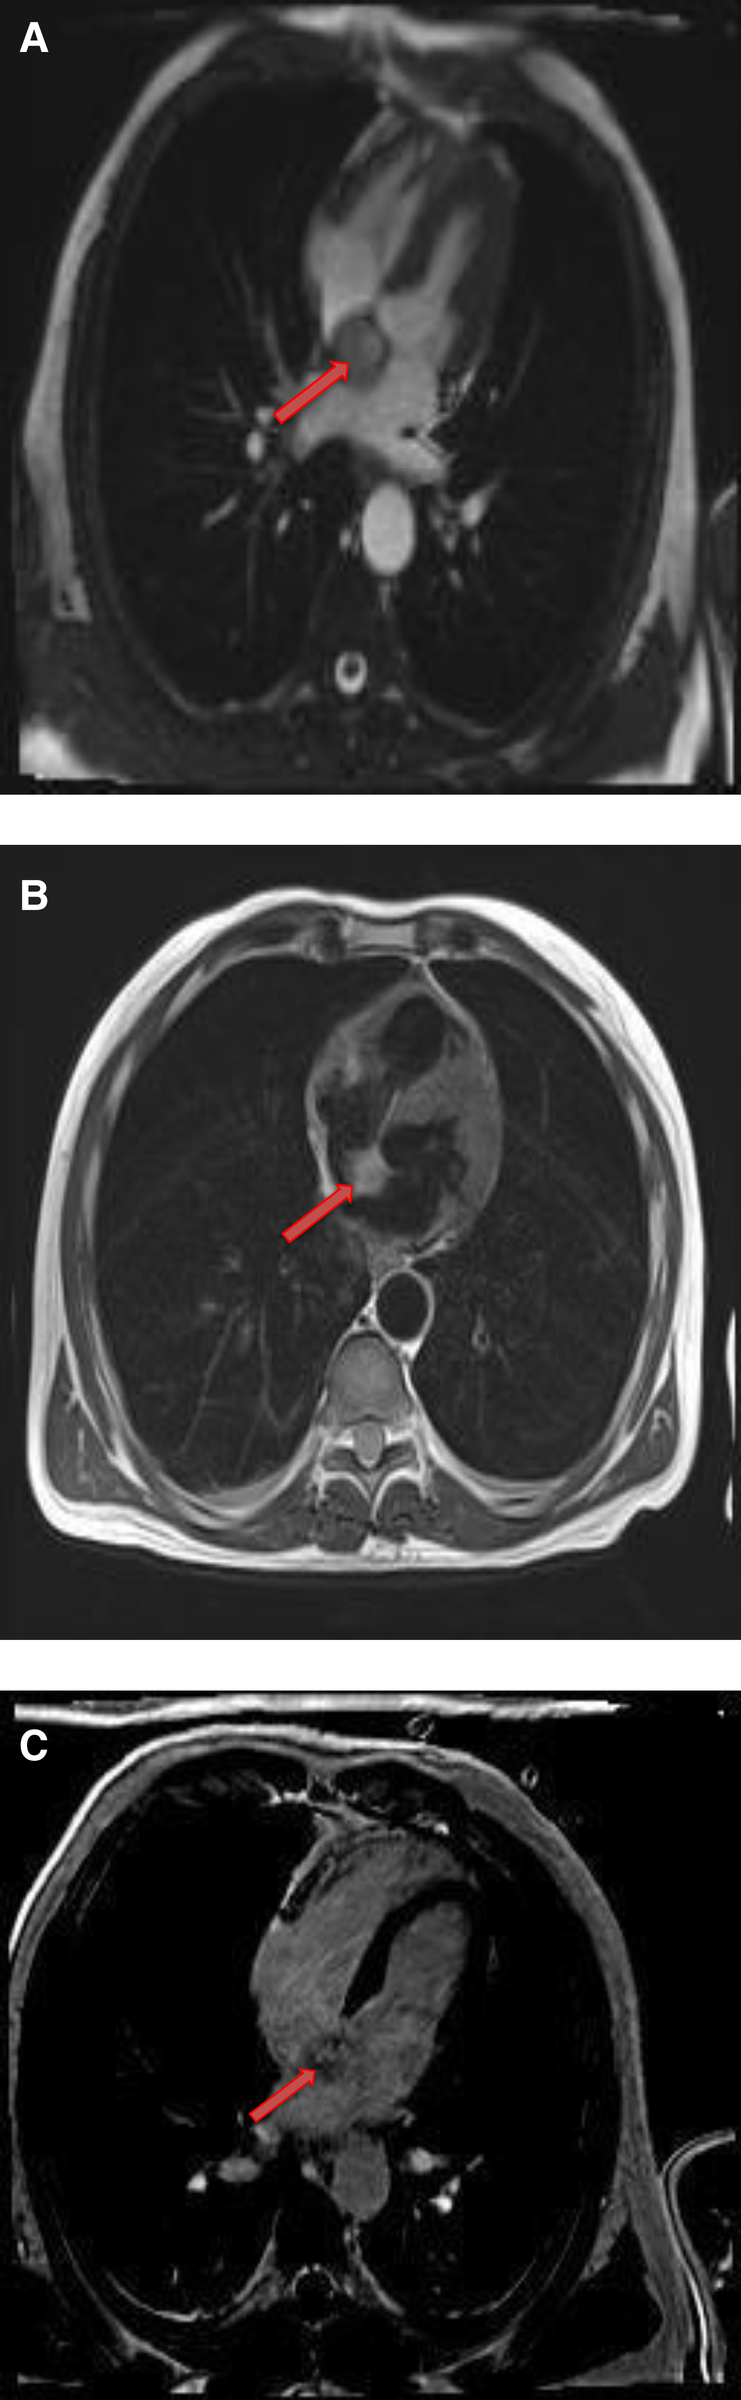

Lipomatous hypertrophy of the interatrial septum is a benign, non-encapsulated, nonneoplastic condition characterized by adipose cell hyperplasia in that region and is often found in older, overweight individuals (34). Lipomatous hypertrophy has the same signal characteristics as lipoma due to their fat content (35). However, lipomatous hypertrophy can be differentiated from lipoma by its morphologic features including larger than 2 cm size, typical involvement of the limbus of fossa ovalis that give rise to a characteristic “bilobed dumbbell appearance” (36) (Figures 5, 6). Most of the patients remain asymptomatic, but there are reported cases of atrial arrhythmias.

Figure 5

A 53-year-old male with lipomatous hypertrophy of the intra-atrial septum. (A) Cine CMR images showing diffuse enlargement and fatty replacement of the intra-atrial septum, consistent with lipomatous hypertrophy of the intra-atrial septum (red arrow). (B) Characteristic “dumbbell shaped” appearance of the mass on axial dark blood, double inversion recovery fast spin echo images (red arrow).

Figure 6

A 61-year-old male with lipomatous hypertrophy of the intra-atrial septum. (A) Cine CMR images showing diffuse enlargement and fatty replacement of the intra-atrial septum, consistent with lipomatous hypertrophy of the intra-atrial septum (red arrow). (B) Characteristic “dumbbell shaped” appearance of the mass on axial dark blood, double inversion recovery fast spin echo images (red arrow).

4.2.1. Cardiac MRI features

CMR provides a definitive diagnosis of both lipoma and lipomatous hypertrophy. Lipomas typically have a homogeneous appearance on CMR. Characteristically, they have the same signal intensity as surrounding chest wall fat on both T1- and T2-weighted images. Additionally, two extremely useful sequences are pre and post contrast fat saturated T1 Weighted sequences. Characteristically, signal dropout is observed on these sequences confirming the diagnosis of a fat-containing lesion. Due to their avascular nature, they do not show contrast enhancement on LGE images (Table 1 and Figures 7, 8).

Figure 7

A 68-year-old female with intra-atrial septal lipoma. (A) (On line video 3), CMR cine images showing a sharply marginated mass arising from the intraatrial septum (red arrow). (B) This mass has same signal intensity (high) as surrounding fat on axial T1-weighted, dark blood, double inversion recovery fast spin echo images (red arrow). (C) Fat suppression sequence representing suppression of surrounding fat (white arrow) as well as the mass in the intra-atrial septum (red arrow).

Figure 8

A 50-year-old female with intra-atrial septal lipoma. (A) This mass has signal intensity (high) as surrounding fat on axial T2-weighted, dark blood, double inversion recovery fast spin echo images (red arrow). (B) This mass is suppressed on axial triple inversion recovery images (red arrow). (C) Complete absence of contrast agent uptake on late gadolinium enhanced images (red arrow).